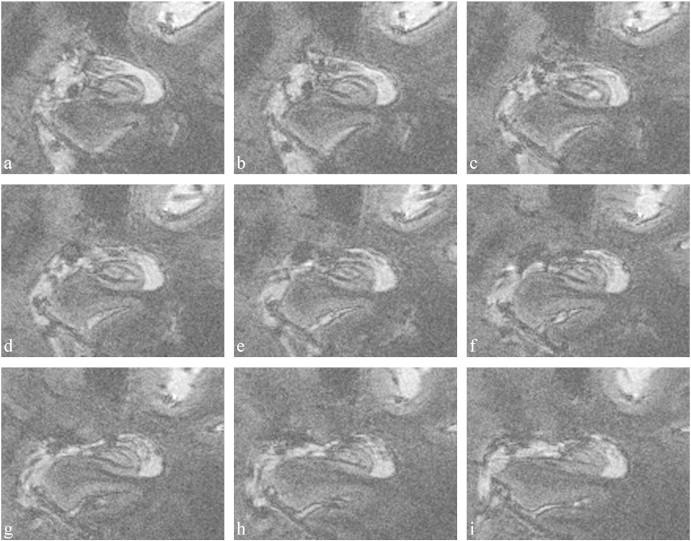

In Alzheimer's disease (AD), the hippocampus is an early site of tau pathology and neurodegeneration. Histological studies have shown that lesions are not uniformly distributed within the hippocampus. Moreover, alterations of different hippocampal layers may reflect distinct pathological processes. 7 T MRI dramatically improves the visualization of hippocampal subregions and layers. In this study, we aimed to assess whether 7 T MRI can detect volumetric changes in hippocampal layers in vivo in patients with AD. We studied four AD patients and seven control subjects. MR images were acquired using a whole-body 7 T scanner with an eight channel transmit-receive coil. Hippocampal subregions were manually segmented from coronal T2*-weighted gradient echo images with 0.3 × 0.3 × 1.2 mm3 resolution using a protocol that distinguishes between layers richer or poorer in neuronal bodies. Five subregions were segmented in the region of the hippocampal body: alveus, strata radiatum, lacunosum and moleculare (SRLM) of the cornu Ammonis (CA), hilum, stratum pyramidale of CA and stratum pyramidale of the subiculum. We found strong bilateral reductions in the SRLM of the cornu Ammonis and in the stratum pyramidale of the subiculum (p < 0.05), with average cross-sectional area reductions ranging from -29% to -49%. These results show that it is possible to detect volume loss in distinct hippocampal layers using segmentation of 7 T MRI. 7 T MRI-based segmentation is a promising tool for AD research.

在阿尔茨海默病(AD)中,海马体是 tau 病理学和神经退行性变的早期部位。组织学研究表明,病变在海马体内不是均匀分布的。此外,不同海马层的改变可能反映了不同的病理过程。7T MRI 极大地提高了海马亚区和层的可视化程度。在这项研究中,我们旨在评估 7T MRI 是否可以在 AD 患者体内活体检测海马层的体积变化。我们研究了 4 名 AD 患者和 7 名对照受试者。使用全身 7T 扫描仪和 8 通道发射接收线圈采集 MR 图像。使用区分神经元体丰富或贫乏的层的协议,从冠状 T2*-加权梯度回波图像手动分割海马亚区,分辨率为 0.3×0.3×1.2mm3。在海马体区域中分割了五个亚区:齿状回的内分子层、放射层、腔隙层和分子层(SRLM)、门区、CA 的锥体层和 subiculum 的锥体层。我们发现 SRLM 的双侧明显减少,以及 subiculum 的 CA 的锥体层(p<0.05),平均横截面积减少范围从-29%到-49%。这些结果表明,使用 7T MRI 的分割可以检测到不同海马层的体积损失。基于 7T MRI 的分割是 AD 研究的有前途的工具。